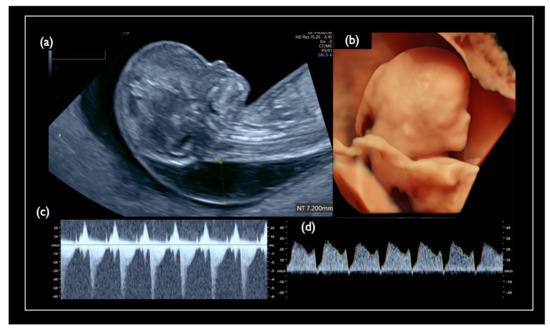

| Chromosome 18 relevant mosaicism | Mo5 | 13 + 5 | XX,+18 Mosaicism | T18 (56%) | 47,XX,+18/46,XX (44%/56%) | – | – | T18 Negative | 2.09 | + | 8.3 | Increased NT, GE moderate, Small NB, Micrognathia, Lowset ear, T18 like profile, Wrist contracture bilateral, Cardiomegaly, Large VSD, TR severe, MR severe, Stomach invisible, Hyperechoic bowel, DV reversed flow, SUA, Umb.A.reverse, T18 is strongly suspected, |

| NC3 | 13w1d | CVS | 25.8 | 47,XY,+18 | No Call | + | 10.6 | Increased NT, CH, GE, Small NB, Micrognathia, Lowset ear, Hypoplastic ear, Cleft lip (left), Maxillary gap, Mild wrist contracture bilateral, RV>LV, TR, DV reverse, Bradycardia, T18 is strongly suspected |